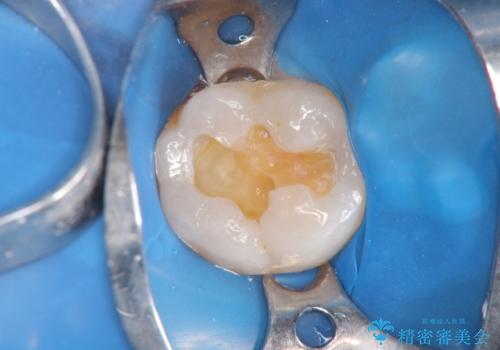

- 痛くて噛めない、これまでだましだまし治療をしてきたがこれを機にすべてきっちりと治したい、口の中の悩みを解決したいと来院されました。

抜歯や歯周病治療、欠損補綴を含め、全顎的な治療を計画・提案します。

口腔内に歯の破折や歯周病、虫歯、欠損など複数の問題が存在する場合局所的に問題を解決していくのではなく全顎的な治療を行っていくことで長期的な予後を見込むことができます。